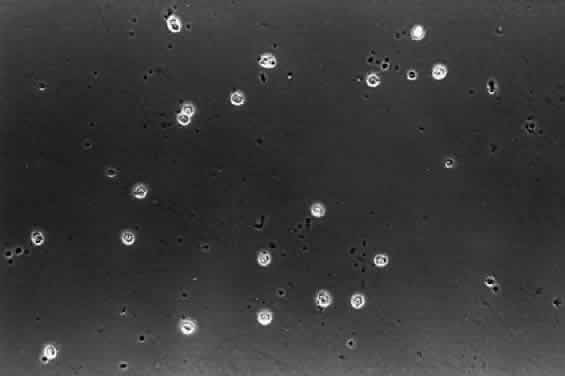

HYALOCYTES.

There are cells embedded within the posterior vitreous cortex (Fig. 18) known as hyalocytes. Situated 20 to 50 μm from the ILL of the retina, these mononuclear cells are widely spread apart in a single layer (Fig. 19). The highest density of hyalocytes is in the region of the vitreous base, followed by the posterior pole, with the lowest density at the equator. Derived from circulating monocytes and renewed every 6 months, hyalocytes are oval or spindle-shaped and are 10 to 15 μm in diameter. They contain a lobulated nucleus, a well-developed Golgi complex, smooth and rough endoplasmic reticula, many large periodic acid-Schiff-positive lysosomal granules, and phagosomes (Fig. 20). Balazs72 noted that hyalocytes are located in the region of highest HA concentration and suggested that these cells may be responsible for vitreous HA synthesis, which may also be true of vitreous collagen.

Fig. 19. Human hyalocytes in situ. Phase-contrast microscopy of flat-mount preparation of posterior vitreous cortex from the eye of an 11-year-old girl obtained at autopsy (courtesy of New England Eye Bank, Boston, MA). No stains or dyes were used in this preparation. Mononuclear cells are distributed in a single layer within the vitreous cortex (7times;115).

Fig. 20. Ultrastructure of human hyalocyte. A mononuclear cell is seen embedded within the dense collagen fibril (black C) network of the vitreous cortex. There is a lobulated nucleus (N) with a dense marginal chromatin (white C). In the cytoplasm, there are mithochondria (M), dense granules (arrows), vacuoles (V), and microvilli (Mi). (×11,670.) (Courtesy of Joe Craft and Dan Albert, MD)

The phagocytic capacity of hyalocytes derives from the presence of pinocytic vesicles, phagosomes (Fig. 20), and cell membrane receptors that bind immunoglobulin G (IgG) and complement. It is intriguing to consider that hyalocytes are among the first cells to be exposed to any migratory or mitogenic stimuli released during various disease states. Because hyalocytes are essentially tissue macrophages, they may have a role similar to macrophages in other diseases, i.e., to recruit cells and elicit further escalation of the inflammatory response. Whereas in some tissues this may be desirable, in the vitreous this process results in various untoward events, depending on the clinical circumstances. In the case of pars planitis, hyalocytes in the vitreous base may be responsible for antigen processing and eliciting an immune response typical of tissue macrophages that leads to the observed snow banks of inflammatory cells in the peripheral anterior vitreous. Indeed, for these and other reasons, this condition may be more aptly named peripheral anterior vitritis. After failed surgery for rhegmatogenous RD, hyalocytes are likely the first cells to participate in the formation of the contractile membranes that in PVR detach the retina again. The particularly high density of hyalocytes in the vitreous base may be important in the pathogenesis of anterior PVR, wherein the prominence of vitreous fibers also contributes to the disease process by facilitating cell migration and transmitting traction to the peripheral retina, ciliary body, and iris. Thus, the role of these cells must be adequately considered in defining the pathophysiology of PVR, perhaps leading to a new avenue for early intervention.